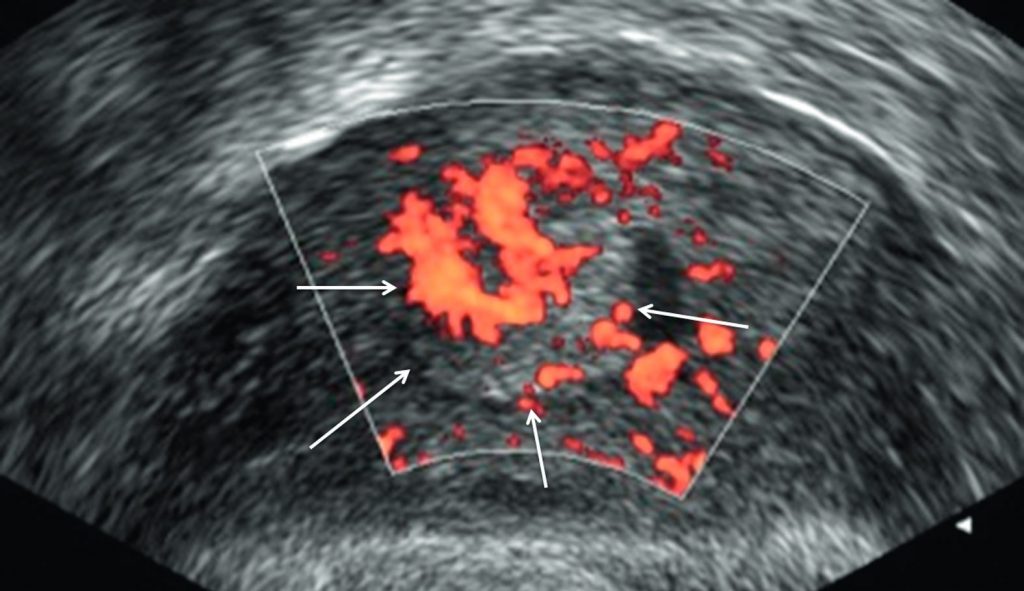

En échographie, un épaississement endométrial supérieur à 4 mm impose la réalisation d’une hystéroscopie diagnostique avec biopsies pour rechercher un cancer sous-jacent. Plus l’épaississement est important et vascularisé en doppler couleur, plus le risque de malignité est élevé (figure 22.2).

Fig. 22.2 Échographie par voie endovaginale en coupe sagittale médiane retrouvant un épaississement suspect de l’endomètre hypervascularisé en doppler énergie (flèches).

Source : CERF, CNEBMN, 2022.